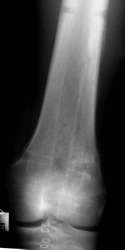

Acht Monate nach der Operation wurde das Metall entfernt.

Die Entfernung durch das Knie hindurch machte keine Probleme. Der

Patient konnte nach 8 Tagen das Knie wieder frei bewegen. Da das Wachstum

weitgehend abgeschlossen war, gab es keine Beinlängendifferenz.